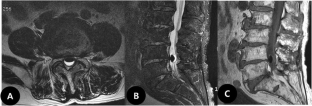

Increased size of a gas-filled intradural cyst causing acute foot drop: a case report

We describe the case of a 76-year-old man presenting with a gas-filled intradural cyst that increased in size over a 10-month period and caused acute bilateral foot drop. The gas-filled intradural cyst was resected from the adherent cauda equina, and histopathological examination identified cystic tissue with degenerated fibrocartilage. Leg pain disappeared immediately following surgery, and the bilateral foot drop resolved within 8 months.

Fig. 2